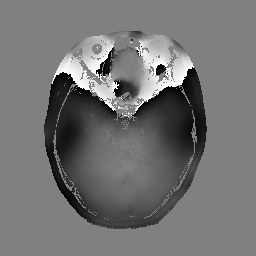

In the first set of evaluations, we considered the reconstruction of an MR image from -undersampled k-space data. The gold-standard magnitude and phase images, which were obtained from a real fully-sampled in vivo T1-weighted MRI acquisition with in-plane matrix size, are shown in Fig. 1. This figure also shows the k-space sampling mask (corresponding to undersampling) that we used to simulate an accelerated acquisition.

For this simulation, the original fully-sampled k-space data (originally measured with 32 channels) was coil-compressed down to 8 virtual channels to reduce computational complexity, and was then retrospectively undersampled using the aforementioned k-space sampling mask. For reconstruction, the matrix was chosen according to the standard SENSE model [41], with sensitivity maps estimated using ESPIRiT [42]. The magnitude regularization took the form of an penalty as given by Eq. (40), where, following Ref. [8], the sparsifying transform was chosen to be the unitary Daubechies-4 wavelet transform. The phase regularization took the form of a Huber-function penalty as given by Eq. (41), where the Huber parameter was chosen to be a small number (i.e., ) in order to approximate the -norm. Following Ref. [8], the transform we used for phase regularization was also a unitary Daubechies-4 wavelet transform. All three algorithms were initialized by applying SENSE-based coil-combination to the multi-channel images obtained by zero-filling the unmeasured data.